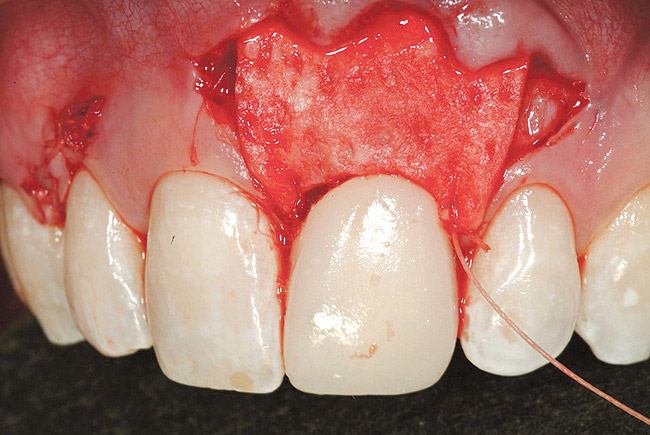

Following the surgical technique previously referenced26 with some modifications, intrasulcular incisions were made around each tooth to be treated to a minimum of one tooth on each side of the affected teeth. The incision was not carried through the entire papillae apical to the contact point, roughly being contained between the mesial and distal line angle of each affected tooth. After the incisions were made, instruments to create a tunnel under each of the incised portions of the papillae were utilized to elevate the base of the papillae. The pouch was then created by blunt dissection using a mucoperiosteal elevator extending the reflection apically past the muco­gingival junction, and laterally to the facial aspect of the tunneled papillae. Occasionally, the papillae may separate in this process, as was the situation in this case. Deepening and mobilization of the pouch was then accomplished by sharp supraperiosteal dissection, which would allow for the pouch to be coronally advanced and cover the dermal tissue completely.

The AlloDerm material, which had been re-hydrated and enhanced with the non-activated PRP solution, was then placed into the surgical pouch with the basement membrane adjacent to the root surface (Figure 7). The dermal matrix was then secured with 6.0 polypropylene sutures (Figure 8). The graft should be positioned at the cemento-enamel junction. The pouch was then coronally advanced to cover the dermal matrix graft completely, and secured with 5.0 monocryl or 6.0 polypropylene sutures (Figure 9). The sutures were removed 1 month postoperatively; note that the need for a topical anesthetic may be necessary for patient comfort during suture removal.

Figure 7  Case One Acellular dermal matrix placed into a "pouch.

Figure 7